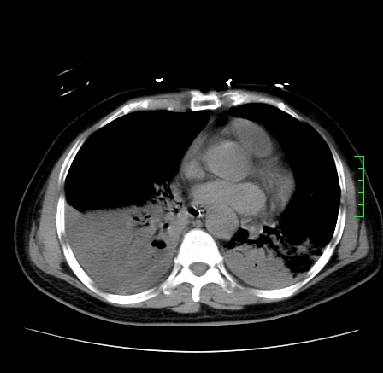

icu病人,几天都没明确诊断。m,76y,咳嗽、咳痰1周,伴气促,右胸痛入院,pe:t38.3c p135 r25 bp135/85。双肺可闻及大量湿罗音,心、腹未见明显异常。诊断:1心衰?2肺部感染?3冠心病?

11号ct

1)两肺感染性病变(右肺下叶肺脓肿可能)。2)双侧胸腔积液,以右侧为甚。

考虑双肺感染、右肺下叶肺脓肿伴双侧胸腔积液。

考虑双肺感染、右肺下叶肺脓肿伴双侧胸腔积液,肺水肿。

考虑:双肺感染、右肺下叶肺脓肿,双侧胸腔积液,肺水肿.请结合临床.